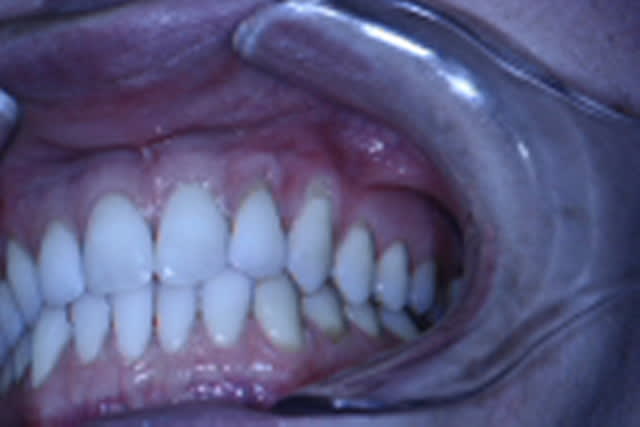

J'hésite sur le choix de la technique.

La patiente est jeune, non fumeuse, aucun problème de santé et très préoccupée par son problème de gencive.

En clair très motivée.

Les récessions sont des Cl I de Miller, donc bon pronostic.

Je penchais pour un conjonctif sur 23 et un lambeau semi-lunaire positionné coronairement sur la 22.

Mais dans une même séance ça paraît difficile.